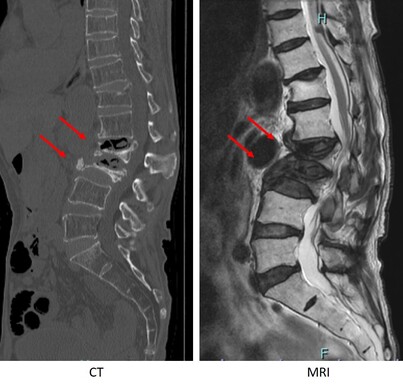

第2腰椎と第3腰椎に高度の骨粗鬆性椎体骨折を認めます。連鎖した骨折椎体は原型を失い扁平化・楔状化を来し、強い腰曲がり・脊柱後弯を呈しています。強い腰痛と体幹バランス不良のため歩行不能でした。MRIでは神経が強く圧迫されているのが分かります。

圧潰して原型を失った第2腰椎と第3腰椎に対して前方進入椎体置換術を行い、後方から広範囲矯正固定術を行っています。亀背は残りましたが、腰痛・神経症状は大幅に改善して杖で歩くことができるようになりました。